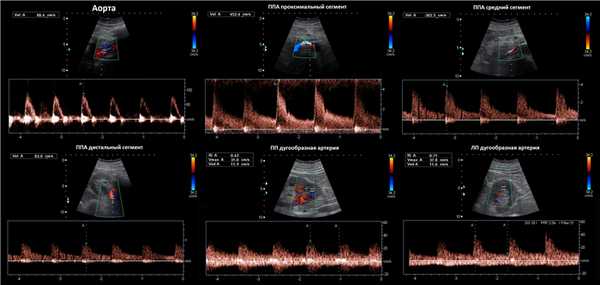

Доплер сосудов почки в норме

Почечную артерию следует оценивать в семи точках: при выходе из аорты, в проксимальном, среднем и дистальном сегментах, а так же верхушечную, среднюю и нижнюю сегментарные артерии. Оцениваем пиковую систолическую (PSV) и конечно-диастолическую (EDV) скорости кровотока, индекс резистивности (RI), время ускорения (АТ), индекс ускорения (PSV/АТ). Подробнее смотри Доплер сосудов.

Нормальный спектр почечных артерий имеет выраженный систолический пик с антеградным диастолическим потоком на протяжении всего сердечного цикла. У взрослых в норме на главной почечной артерии PSV 100±20 см/сек, EDV — 25-50 см/сек, у детей раннего возраста PSV 40-90 см/сек. В сегментарных артериях PSV падает до 30 см/сек, в междолевых до 25 см/сек, в дуговых до 15 см/сек и междольковых до 10 см/сек. RI в воротах почки

Рисунок. Нормальный спектр почечных артерий — высокий систолический пик, антеградный диастолический поток, низкое периферическое сопротивление — RI в норме